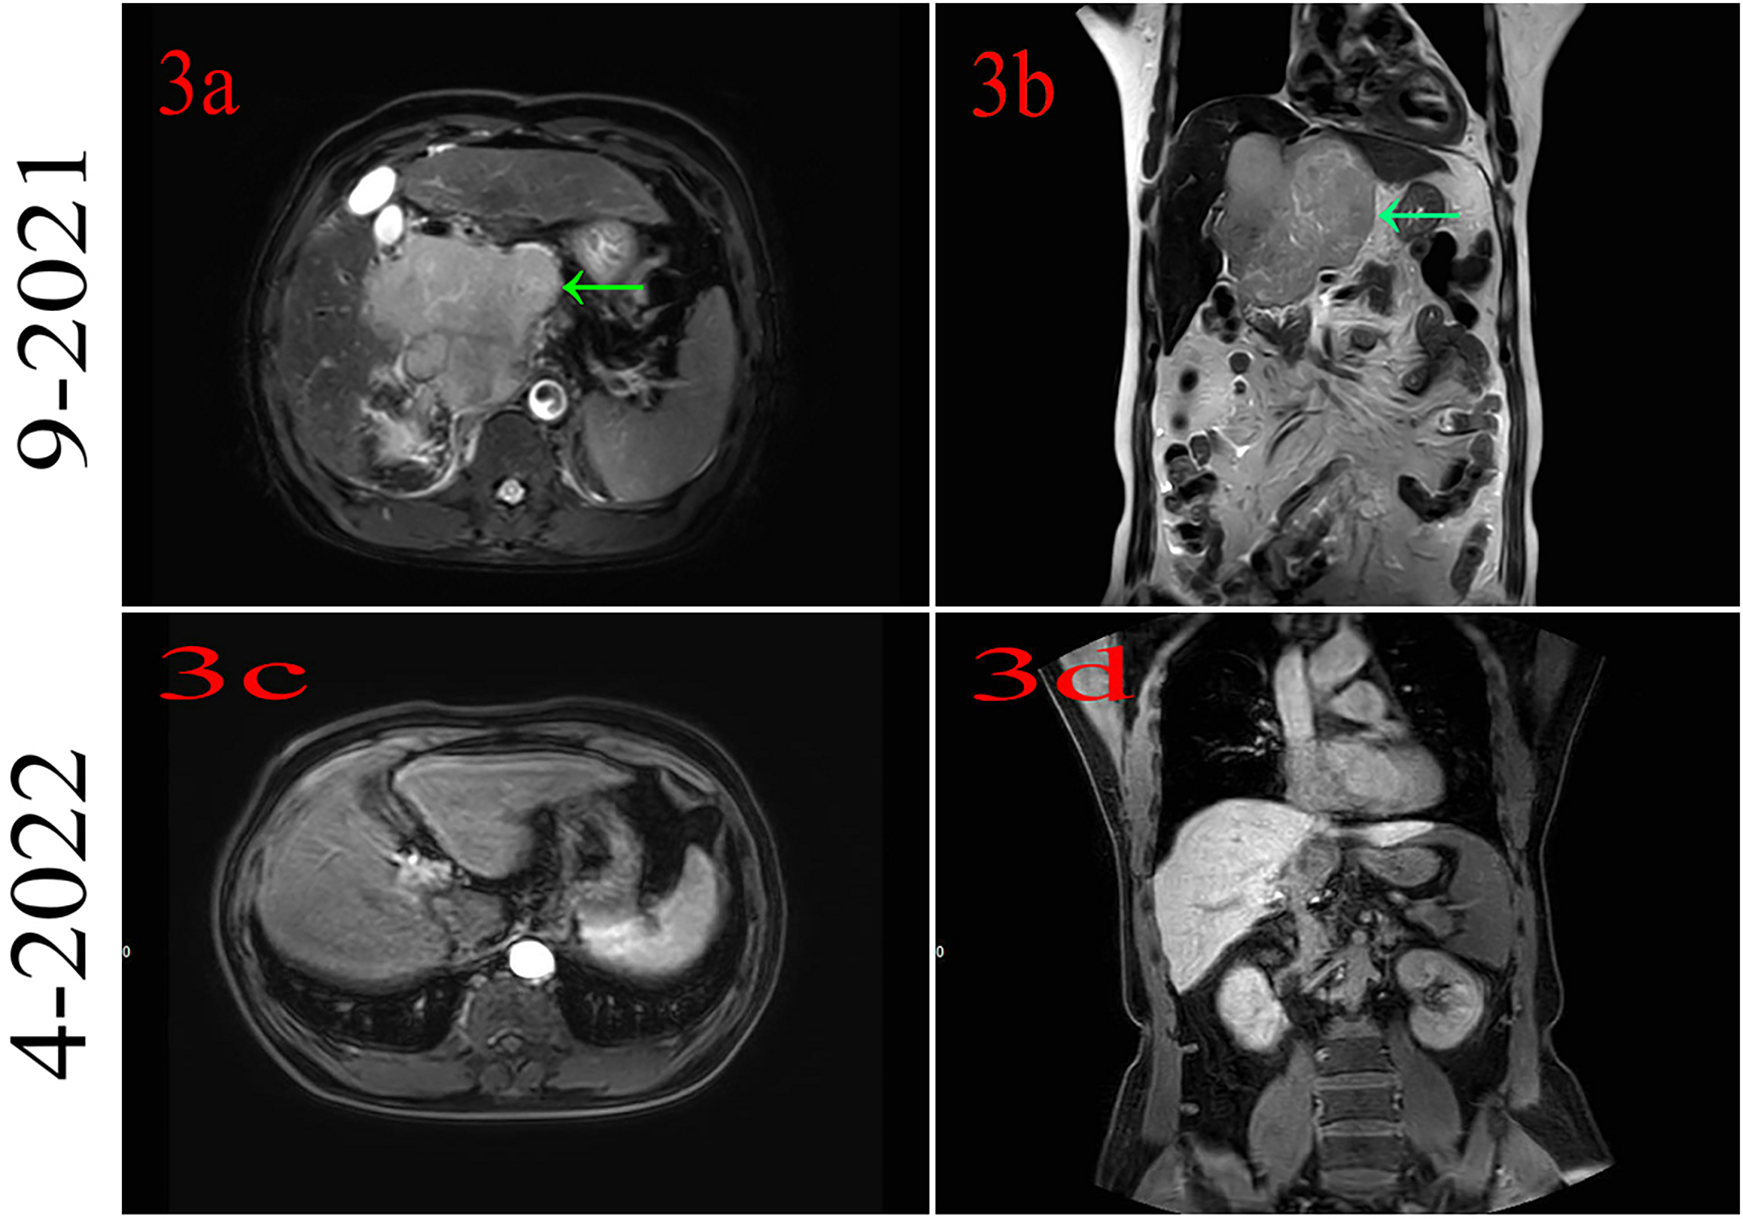

The patient had no family history of cancer or infectious disease but had a history of long-term alcohol consumption. In September 2021, the patient underwent a physical examination, and solid lesions were found in his liver. Subsequently, a laboratory examination found abnormal levels of alpha-fetoprotein (AFB) (9.50 ng/ml; normal: 0–8.78 ng/ml) and protein induced by vitamin K absence or antagonist-II (PIVKA II) (261.29 mAU/ml; normal: 13.62–40.38 mAU/ml). Gadoxetic acid disodium MRI indicated a huge mass in the S1 segment and cancer emboli were found in the right branch of the portal vein and the inferior vena cava (Figures 3a,b). Based on the above information, the patient was diagnosed with HCC and received systemic therapy with PD-1 (sintilimab 200 mg) combined with bevacizumab (600 mg), q3w. The patient achieved complete remission, and the medication was discontinued after 14 cycles (Figures 3c,d).

Figure 3

(a,b) Magnetic resonance imaging indicates hepatocellular cancer at segment 1. (c,d) MRI indicates that the patient had complete remission.